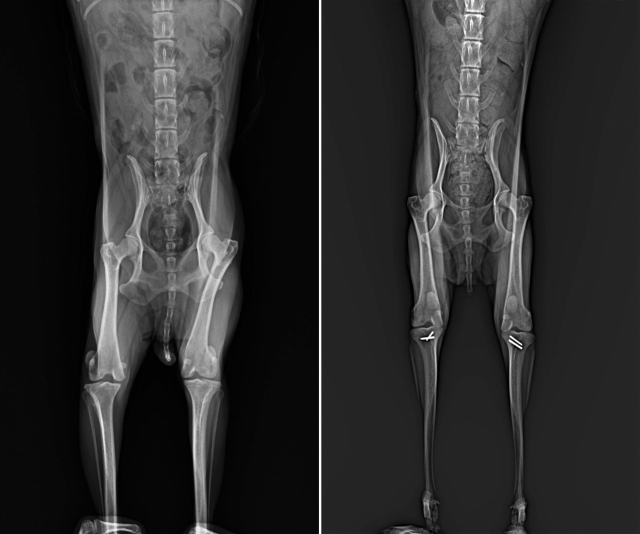

A. 소형견에서 다발하는 슬개골 탈구는 선천적인 요인이 크다. 성장기에 뒷다리가 곧게 성장하지 못하고 'O '자 또는 'X'자 형태로 휘어져 자라다 보니 슬개골 탈구가 발생한다. 뒷다리가 'O' 자 형태로 휘어지면 내측슬개골탈구가, 'X' 자 형태로 휘어지면 외측 슬개골탈구가 발생한다. 성장기 갑작스러운 몸무게 증가와 미끄러운 실내 바닥 생활이 성장기 슬개골 탈구를 악화시키는 부가적인 요인이 되기도 한다.

호야(푸들, 14y, 3kg)는 슬개골 탈구 중에서도 드문 케이스인 슬개골 외측 탈구가 어릴적부터 있어 왔지만 별 다른 보행 불편을 보이지 않아 교정수술을 하 않고 지내왔다. 하지만 수개월 전 부터 보행을 불편해하고 뒷다리를 들고 다니는 상황이 되었다고 한다. 가족들은 나이 많은 호야가 혹시나 수술하다 잘못되지는 않을까 걱정스러워 했다.

호야는 수술에 앞서 마취 전 검사들을 진행했다. 다행히 호야의 건강상태는 마취가 위험한 정도의 심각한 상황은 아니었다. 노령임을 감안하여 안전성이 높은 Sevoflurane 호흡마취가 진행되었으며, 퇴행성관절염과 근위축을 동반한 고령 환자임을 고려하여 관절낭을 손상시키지 않은 채 경골결절을 변위시키는 교정수술을 시술했다.

호야는 수술 3일 째부터 걷기 시작하여 입원 5일 후 퇴원할 수 있었다. 퇴원하더라도 노령견임을 감안하여 기력 회복을 위해서 가족들의 세심한 배려가 필요함을 보호자분에게 당부했다.

호야처럼 노령견이라고 해서 수술을 마냥 피해서는 곤란하다. 마취와 수술에 동반되는 위험 요소들을 신중하게 체크하고 보다 안전한 마취법과 합당한 수술방법을 적용하면 노령견도 안전하게 수술받고 회복할 수 있음을 보여준 사례였다.